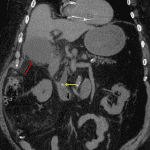

- Marked gallbladder distension with diffuse wall thickening, several calcified stones, and extensive pericholecystic inflammatory changes

- 3 mm hyperattenuating structure in the distal common bile duct near the ampulla

- Inflammatory changes extend about colonic diverticula arising from the hepatic flexure

- Trace free fluid tracks from the right upper quadrant inferiorly along the right paracolic gutter

- Acute cholecystitis with choledocholithiasis

Findings consistent with acute cholecystitis and choledocholithiasis with a small stone suspected in the distal common bile duct near the ampulla.

Inflammatory changes about colonic diverticula arising from the hepatic flexure are likely secondary to the adjacent cholecystitis.